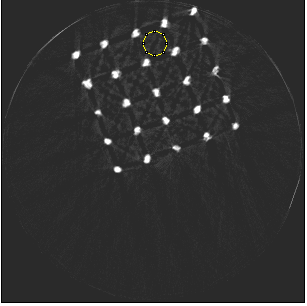

Beam hardening and metal artefacts pose challenges during CT imaging in the presence of metal hardware [17]. This paper presents data that demonstrates the use of spectral imaging in reducing beam hardening effects and metal artefacts. A high-Z sensor layer like CdTe is necessary to provide improved spectral resolution at higher x-ray energies needed for typical implant visualisation. Multi-energy acquisition of metal samples has the added advantage of capturing spectral information which exhibits reduced artefacts and reasonable non-metal (tissue) information. Further, the results were obtained without any hardware filters (except for the intrinsic filter-equivalent in the x-ray tube) and without any numerical corrections. A global reduction in noise due to charge sharing effects was seen due to the availability of CSM. 3D visualisation of the samples (figure 9) revealed finer spatial structures.

Refer to caption

(a) Porous Ti scaffold

(b) Mg scaffold

(c) Ti mesh

Figure 9: High resolution MARS-Exposure Render visualisation of the metal samples